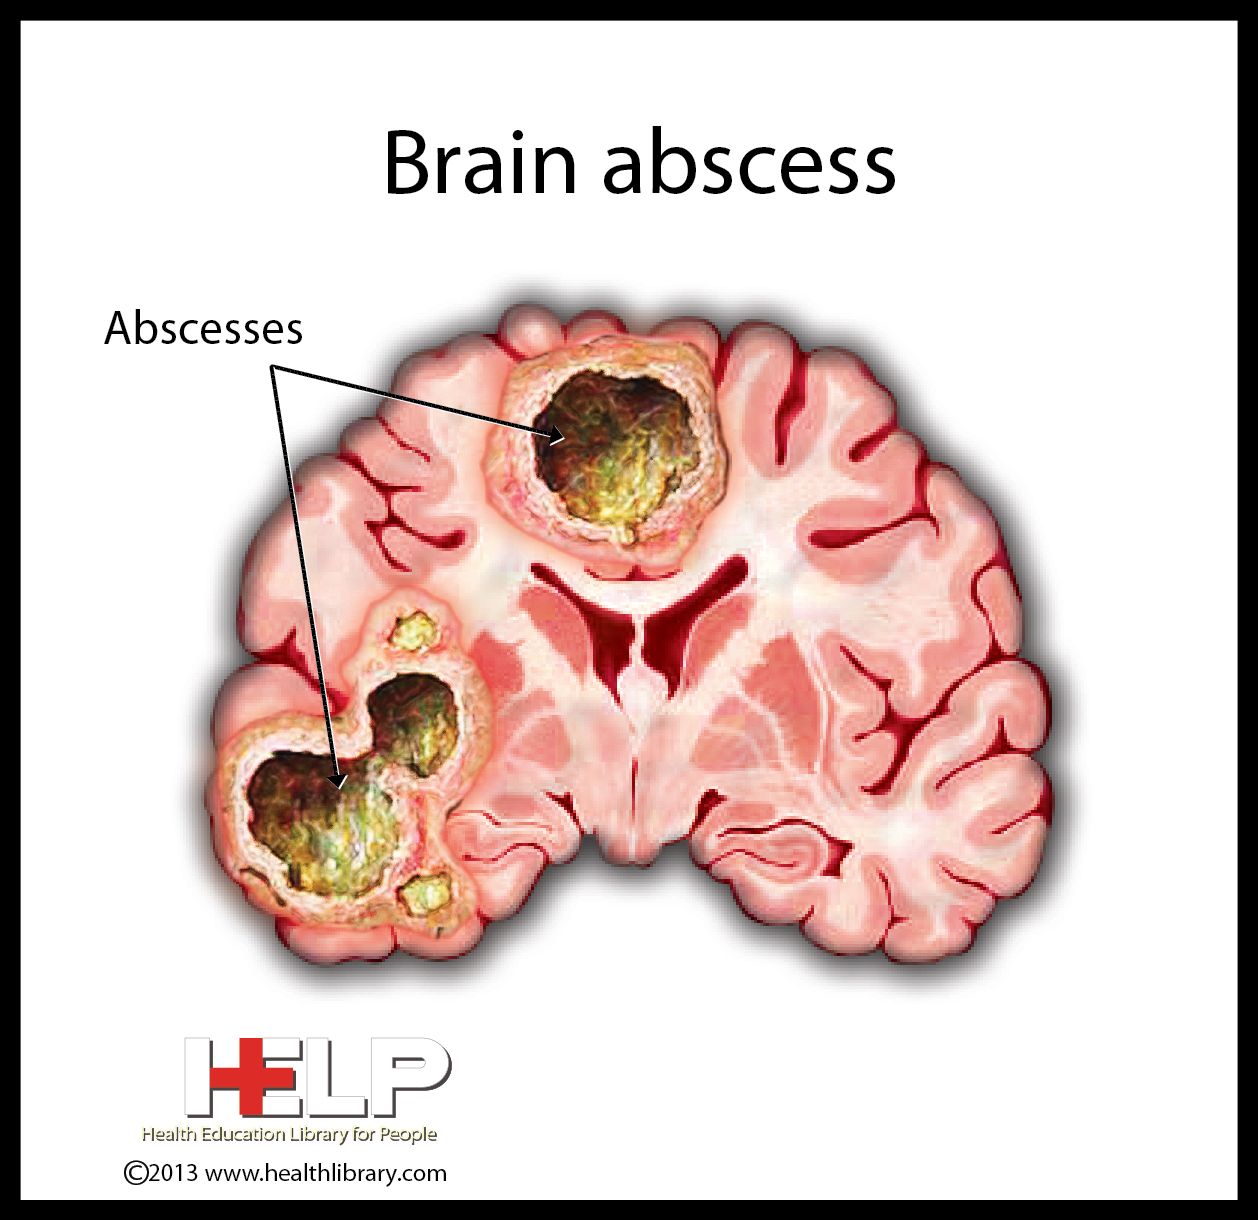

Brain Abscess | Nclex, Nurse practioner, Nclex study